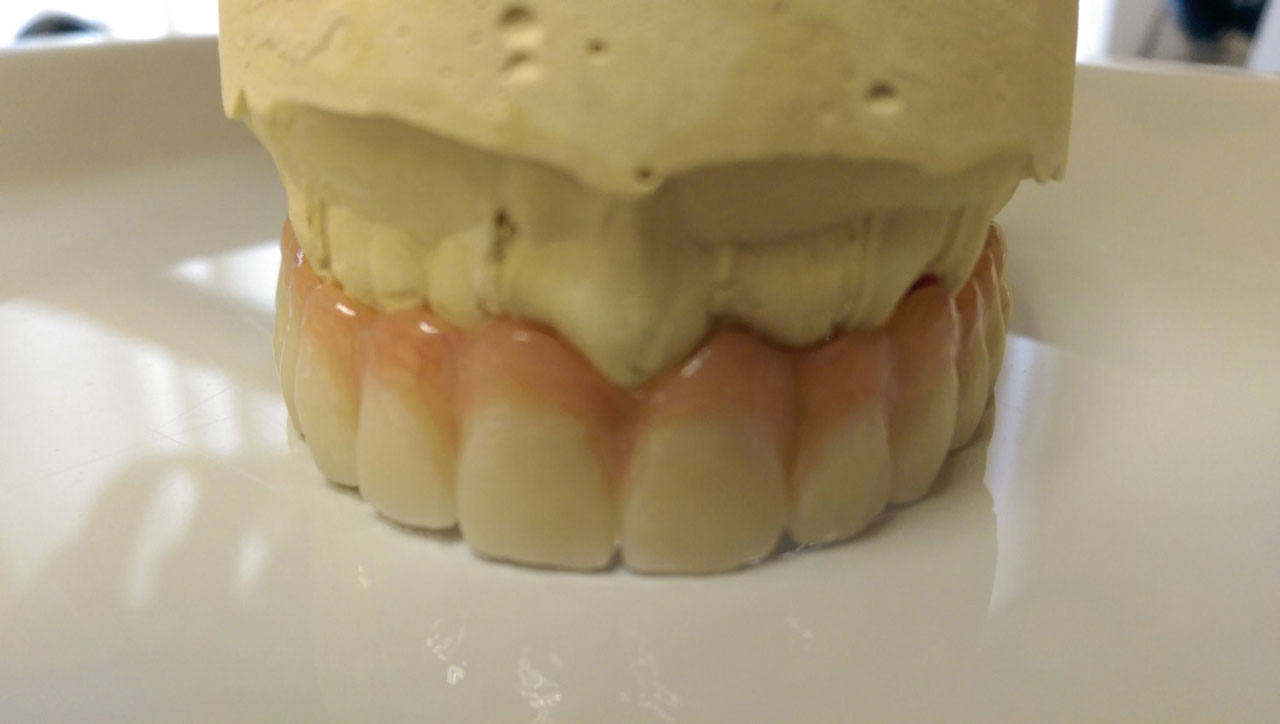

• esettanulmany-40

Így néz ki a hosszútávú ideiglenes híd.(Fém vázzal erősített műanyag híd.)

• esettanulmany-41

Így néz ki a hosszútávú ideiglenes híd. (Fém vázzal erősített műanyag híd.)

• esettanulmany-42